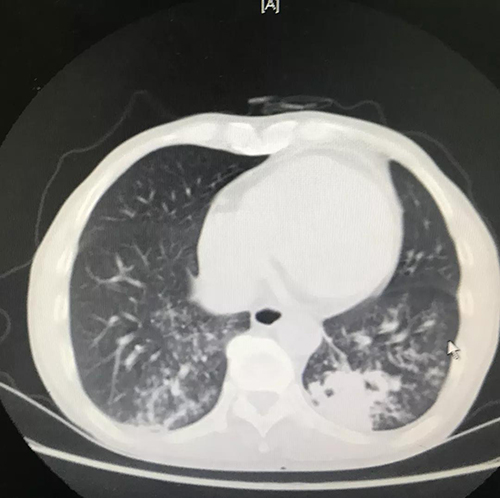

治疗前CT:A瘘口

B肺部感染

患者经硬镜下“Y”型覆膜支架顺利封堵瘘口并充分吸痰,积极抗感染治疗后,患者体温得到有效控制,复查胸部CT炎症明显好转,可自主进食,解决了患者长期以来无法进食及肺部感染的问题,生活质量得到极大提高。患者及家属对治疗效果非常满意。